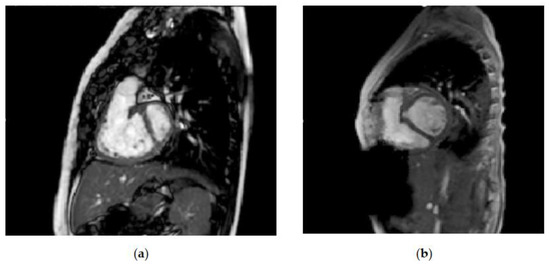

Figure 2 shows the enlargement of the left ventricular volume, from before left ventricular recruitment and after full biventricular conversion, in one of the patients at our center who underwent the staged ventricular recruitment pathway. Note the interventricular septal shift that leads to near-normal relative ventricular volumes. It seems that there is more change than just increased preload leading to septal shift alone. In some studies, the increase in left ventricular dimensions is not associated with a simultaneous decrease in the size of the right ventricle [16]. On top of the volume increases, the indexed left ventricular mass increased, and there was a decrease in the left ventricular mass–volume ratio, since the ventricle responds to volume, as well as to pressure load. The Boston left ventricular recruitment study excluded patients with ventricular septal defects (VSDs). The group at Chiba Children Hospital in Japan discussed their staged biventricular repair-oriented strategy in borderline candidates with VSDs [17]. Importantly, recognizing the limitations of the strategy, they chose patients to undergo biventricular repair by using a risk profile for single-ventricle palliation, rather than by a purely anatomical possibility. They were more likely to follow the staged biventricular repair strategy if there were features that had the potential for increased pulmonary hypertension, i.e., Kartagener syndrome or Trisomy [18]. This was an approach reinforced by Boston, with the evolution of their biventricular repair and left ventricular recruitment program [19]. They performed a study to determine the effect of ASD restriction without VSD closure on ventricular growth in patients with borderline right or left ventricles and VSDs. There were increases in the median indexed ventricular diastolic volume (31.7 mL/m [IQR, 24.5–37.1] to 48.5 mL/m2 [IQR, 38.4–58.0]; p < 0.01) and median indexed systolic volume (13.3 mL/m2 [IQR, 9.7–18.7] to 19.5 mL/m2 [IQR, 16.8–29.7]; p < 0.01). Biventricular conversion was performed in 14 patients (67%), with 2 deaths (14%).

Figure 2. Comparison of left ventricular volumes on magnetic resonance imaging (a) before left ventricular recruitment: left ventricular end-diastolic volume (LVEDV) 12.9 mL, indexed left ventricular end-diastolic volume (LVEDVi) 20.2 mL/m2 and (b) after full biventricular conversion: LVEDV 54 mL and LVEDVi 72 mL/m2.